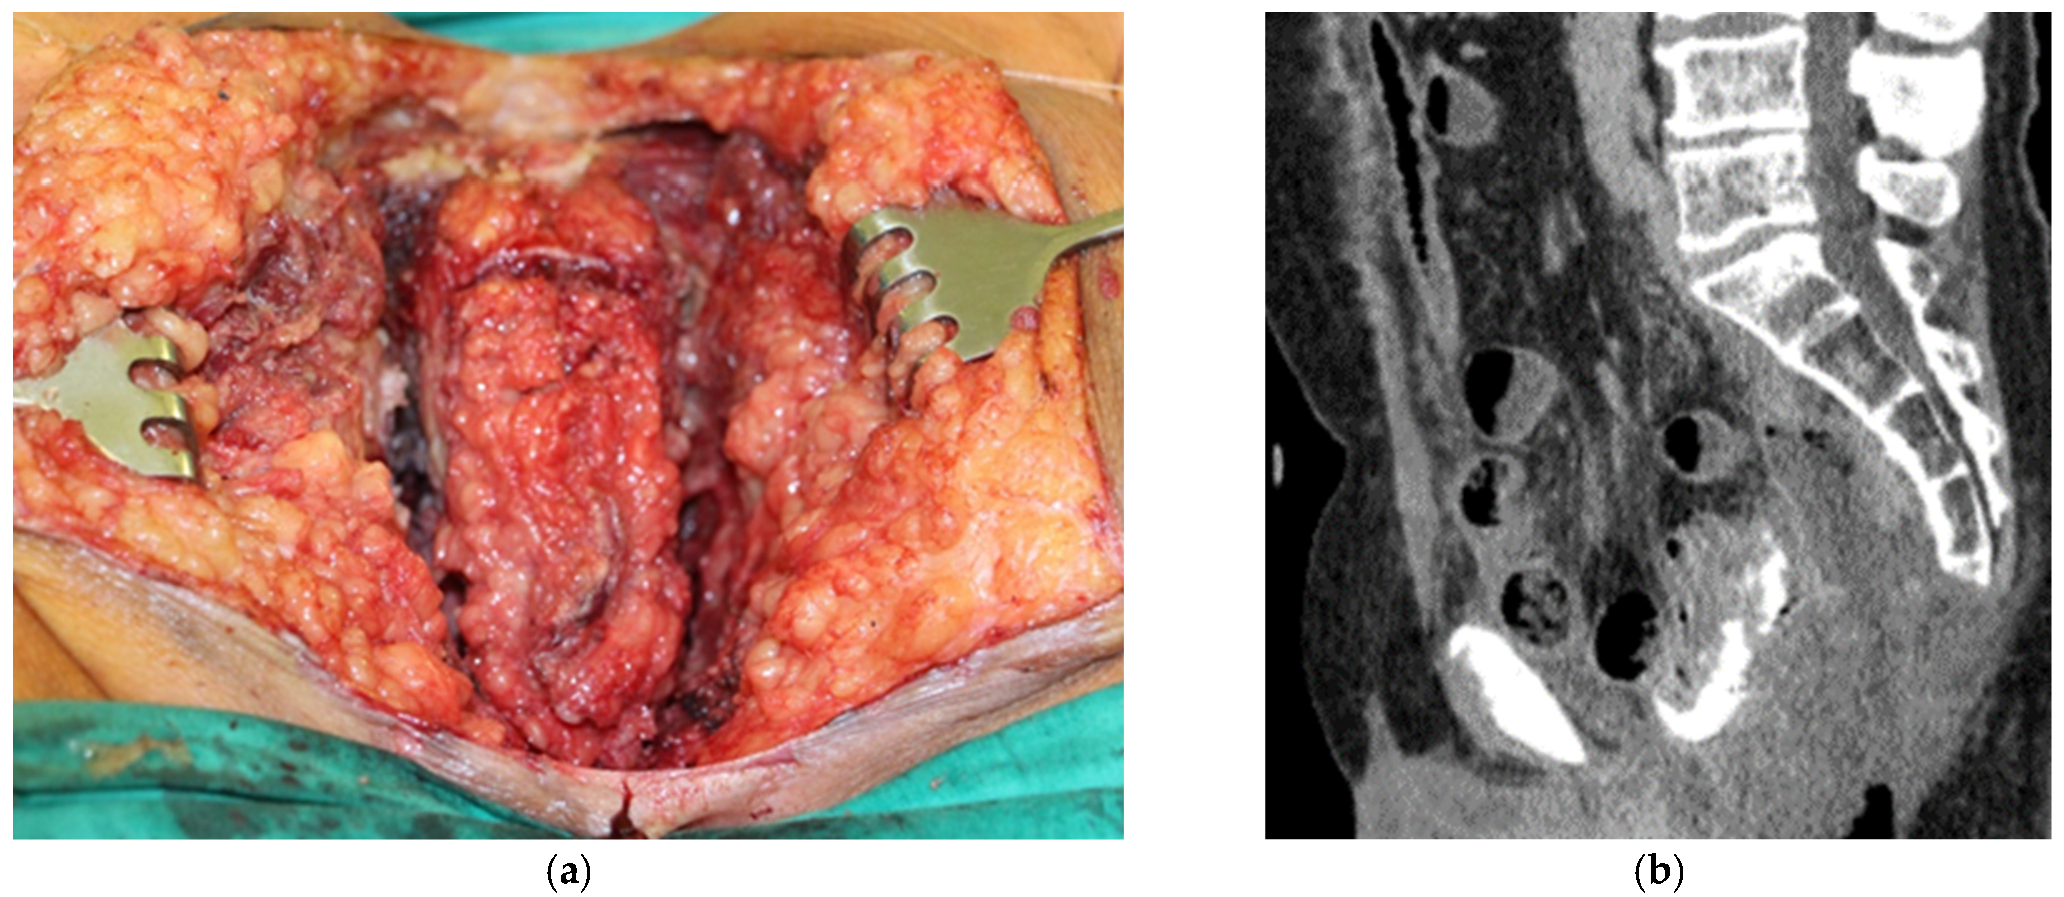

3.1. Clinical Experience in Cases with Invasive Markers

3.2. Clinical Experience in Cases with Noninvasive (Skinbased) Markers